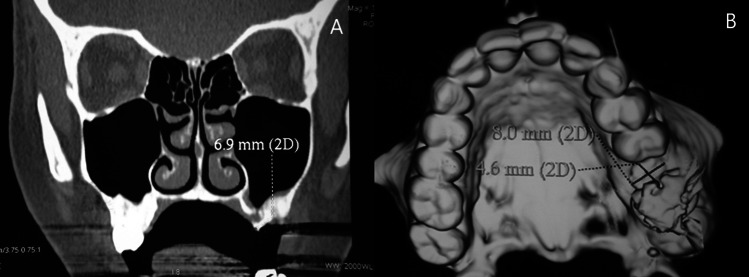

One clinical complication oral surgeons encounter is oroantral communication (OAC) with progressive formation of oroantral fistula (OAF). Among bone grafting materials, autogenous bone is still considered the gold standard in grafting oral and maxillofacial regions. To evaluate clinically and radiographically the efficacy of Calcium phosphate (Vital-Os) bone cement in stabilizing an autogenous bone graft in repairing an oroantral fistula. The study recruited 20 patients with an oroantral fistula ranging from 4-10 mm diameter. Ten patients were treated by grafting the defect with bone graft harvested from the chin area and closure of oroantral by buccal advancement flap and Vital-Os Bone cement (Study group), and ten patients were treated without Vital-Os Bone cement (Control group). All patients came for postoperative follow-up at the 1st, 3rd, and 6th months. Visual Analogue Scale (VAS) in the study group was significantly lower than the control group one week and one month postoperatively (p = .007, .004; respectively). Failure of the oroantral fistula closure was significantly lower in the study group (p = .025). The closure of an oroantral fistula is recommended through the use of an autogenous bone graft harvested from the chin region, supplemented by the application of injectable VitalOs bone cement to secure the graft at the recipient site.